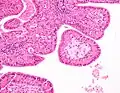

The appearance of this tumor under the microscope is unique. There are cystic spaces surrounded by two uniform rows of oncocytes, which are epithelial cells with abundant, granular, eosinophilic cytoplasm.[7] The cystic spaces have epithelium referred to as papillary infoldings that protrude into them. Additionally, the epithelium has lymphoid stroma with germinal center formation.

Histopathology of Warthin tumor in the parotid gland. Another view of a file "Warthin tumor (1).jpg". H&E stain. -

Histopathology of Warthin tumor in the parotid gland. Higher magnification of a file "Warthin tumor (1).jpg". H&E stain. -